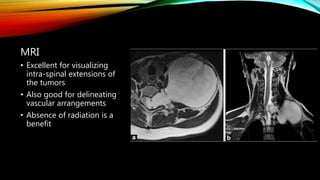

MRI

• Excellent for visualizing

intra-spinal extensions of

the tumors

• Also good for delineating

vascular arrangements

• Absence of radiation is a

benefit